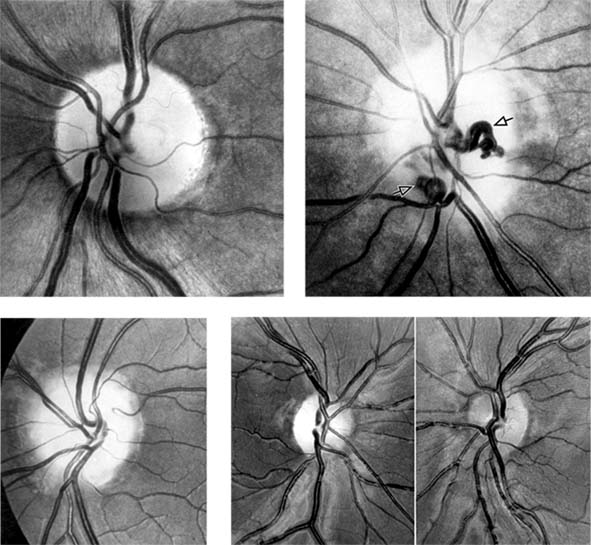

ANTERIOR ISCHEMIC OPTIC NEUROPATHY

Anterior ischemic optic neuropathy is characterized by pallid disk swelling associated with acute loss of vision: often there are one or two peripapillary splinter hemorrhages (Figure 14-13). The disorder is due to infarction of the retrolaminar optic nerve (the region just posterior to the lamina cribrosa) from occlusion or decreased perfusion of the short posterior ciliary arteries. Fluorescein angiography in the acute stage shows decreased perfusion of the optic disk, often segmental in the nonarteritic form but usually diffuse in the arteritic form, and disk leakage in the late phase. There may be associated perfusion defects in the peripapillary choroid.

Figure 14-13

Figure 14-13: Pseudo-Foster Kennedy syndrome due to sequential anterior ischemic optic neuropathy. A: Swollen right optic disk with hemorrhages due to current ischemic episode. B: Atrophy of left optic disk due to previous ischemia. C: Early phase of fluorescein angiogram of right eye showing poor perfusion of optic disk and dilated superficial disk capillaries. D: Late phase of fluorescein angiogram showing disk leakage.

Papilledema is often asymmetric. It may even appear to be unilateral, though fluorescein angiography in such cases usually shows leakage from both disks. Papilledema occurs late in glaucoma, but it will not occur at all if there is optic atrophy or if the optic nerve sheath on that side is not patent. Foster Kennedy's syndrome is papilledema on one side with optic atrophy on the other (optic nerve and sheath compressed by neoplasm). This is commonly due to meningiomas of the sphenoid wing and classically to meningiomas of the olfactory groove. However, this clinical presentation can be mimicked (pseudo-Foster Kennedy syndrome) by ischemic optic neuropathy when an old ischemic optic neuropathy with atrophy is associated with a new hyperemic ischemic optic neuropathy (Figure 14-13).